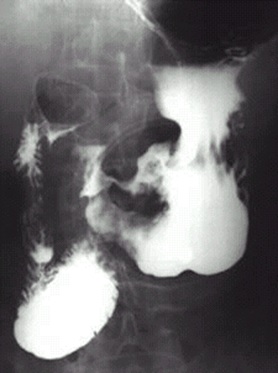

04卷-5.病史:男性,62歲,上腹不適,惡心、嘔吐5個(gè)月,大便潛血陽性3周。診斷

A.十二指腸球潰瘍

B.胃潰瘍

C.胃癌

D.胃炎

【該題針對(duì)“ X線-消化道穿孔 ”知識(shí)點(diǎn)進(jìn)行考核】